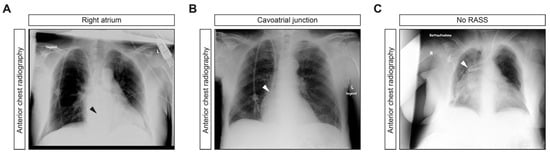

| Chest Radiography Position | RASS | No RASS |

|---|---|---|

| Right atrium—no. (%) | 18 (75) | 0 (0) |

| Cavoatrial junction—no. (%) | 5 (20.8) | 0 (0) |

| Subclavian-caval junction—no. (%) | 0 (0) | 1 (4.2) |